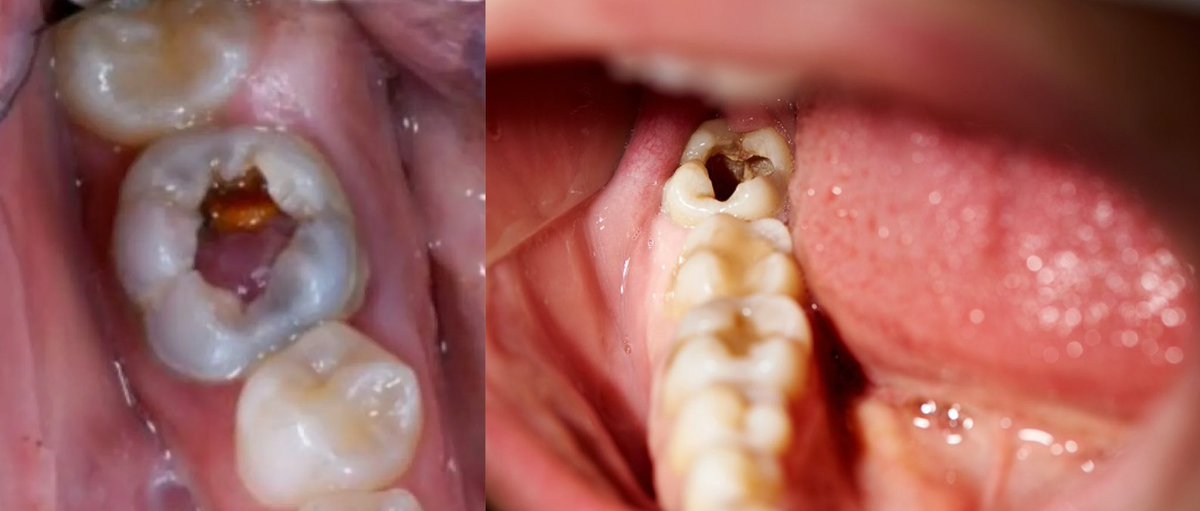

kalau ada yg memiliki keluhan gigi seperti pada foto (gigi berlubang besar dan goyang) dan ingin untuk dilakukan perawatan, boleh DM aku yaa!🦷✨ (area jakpus)

koas jakarta pusat gigi bolong berlubang

#koasgigi #sakitgigi #gigiberlubang #gigibolong #tambalgigi

Halo, saya koas gigi di RSKGM Salemba Jakarta Pusat. Apabila ada keluhan gigi boleh konsul dan dm ya, perawatan gratis!!😄🫶🏻

#koasgigijakarta #gigiberlubang #Doktergigi #perawatansaluranakar #tambalgigi #cabutgigi #cabutgigibungsu #gigipatah #sakitgigi